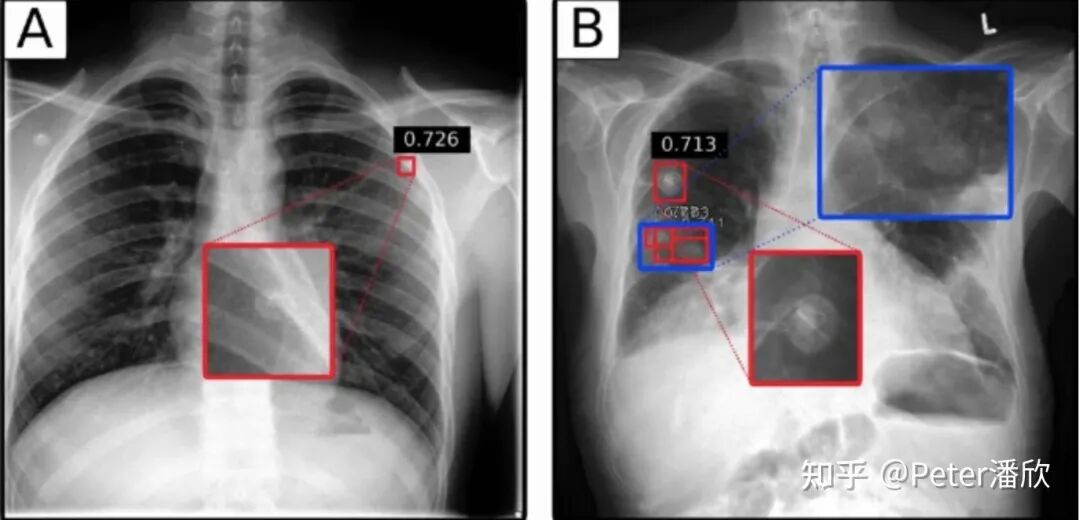

17年Brain下成立一个放射科的医疗影像团队:Radiology。由于我正好在这个领域开发模型,就帮助了这个团队的创建。 最初我们先从简单的XRay下手。我将FasterRCNN先经过CoCo的预训练,然后再几百张XRay样本上做了一些fine-tune,结果意外的好。 后来我们深入到更难的CT场景。CT是对人进行3维立体的扫描,因此对应的框需要包含长宽高。由于当时是兼岗,我简单将CT做了抽帧,转换成多张二维图片,然后通过FasterRCNN,然后再三维化。这样效果比较一般。后来一个韩国小哥实现了一个高性能的3D检测,取得了更好的效果。 花絮 AI医疗的上线是非常困难的,特别是在美国这种FDA管理比较严格的国家。当时我们找到一个场景,据说是不需要FDA Apporve的: 通常需要被诊断的Radiology数据是FIFO排队被医生诊断的。这就有个问题,有可能某个人的情况很紧急(比如车祸胸部骨折),但是他的XRay被排在了后面,耽误了诊断。我们可以用AI模型对这些XRAY做一个严重程度的排序,给医生提出建议。另外,我们还在印度搞了流动医疗车,免费提供相关的诊断。

img